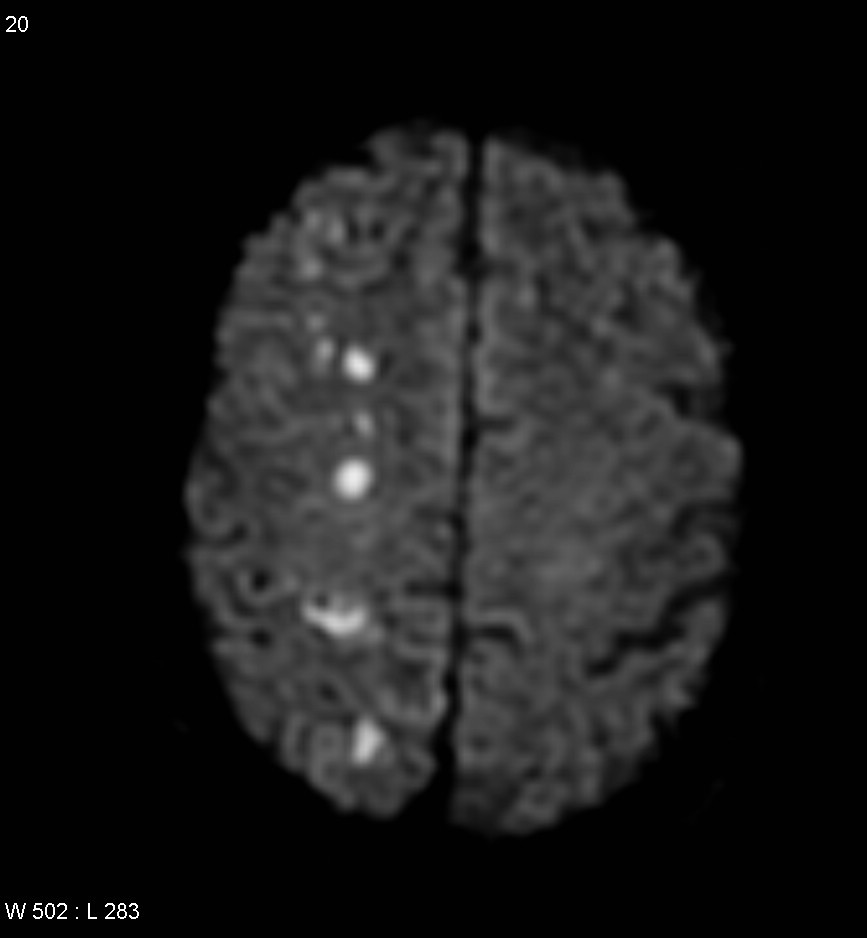

45 y/o woman with hypertension is resuscitated after a cardiac arrest. On day three she is not moving her limbs. An MRI looks like this.

There are multiple areas of watershed in the brain

MCA is most affected in global hypotension

Posterior circulation is rarer

A 20 year old man tries to commit suicide by hanging himself. He is cut down after several minutes and is pulseless. He is resuscitated and regains a heartbeat and respiratory drive and cough to suctioning. Three days later, his exam has not changed.

Where is the lesion?

cortical lamniar necrosis

Neurons survive 6-10 mins w/out oxygen and glial cells last up to mins

glial cells liver 30 mins

astrocytyes live longer